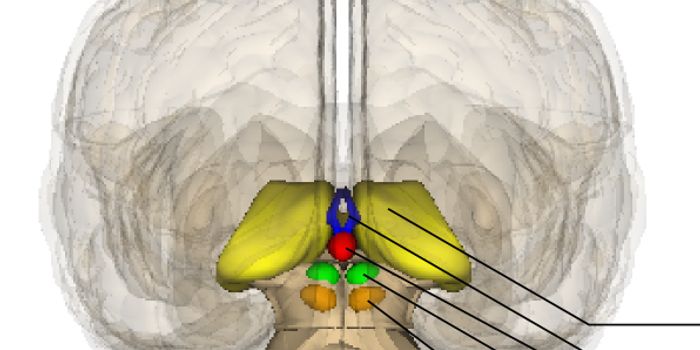

JUN 30, 2016NeuroscienceWhen there has been a traumatic brain injury (TBI) or there is a tumor or other problem in the brain, doctors need to kn ...